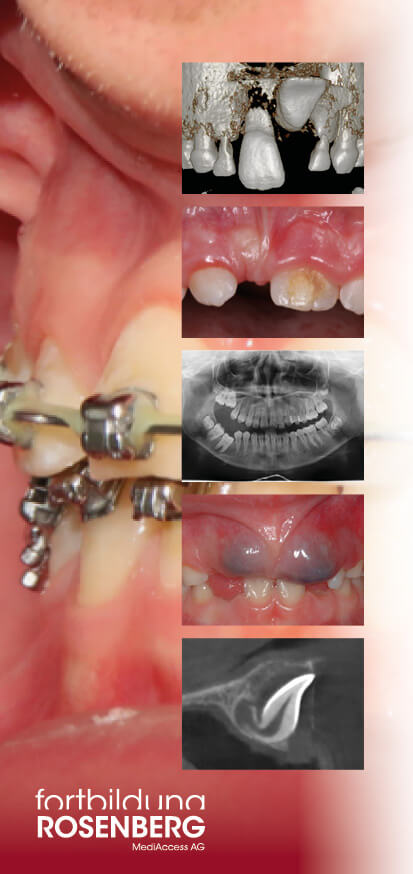

Durchbruchstörungen der Zähne

Mehr Sicherheit im Umgang mit Durchbruchstörungen

Immer wieder wird beobachtet, dass bleibende Zähne nicht oder nicht spontan durchbrechen. Gründe können Hindernisse, Engstand, Ankylose oder follikuläre Zysten sein. Auch nach Zahnunfällen kann es zu Durchbruchstörungen kommen.

Zunehmend häufig werden jedoch Durchbruchstörungen insbesondere der 1. und 2. Molaren beobachtet, die oft auch als PFE (Primary Failure of Eruption) bezeichnet werden. Diese Diagnose wird früh im Leben gestellt, die Retention der Zähne ist oft sehr eindrücklich und die möglichen Therapien sind nicht ganz einfach.

In der Fortbildung werden alle möglichen Ursachen und Therapien von Durchbruchstörungen diskutiert: die chirurgische Freilegung und kieferorthopädische Einordnung, die operative Entfernung, die intentionelle Replantation,die Koronektomie oder Wait & see. Alle Behandlungen werden Step-by-step erklärt, ebenso die Entscheidungskriterien, die für oder gegen die eine oder andere Therapie sprechen.